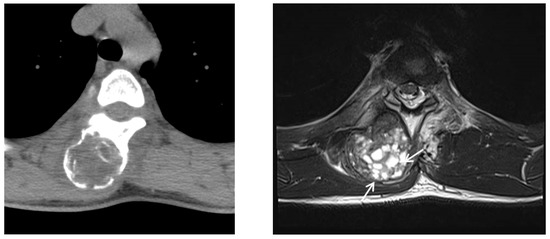

We decided to discharge and observe the patient without surgical intervention. However, follow-up thoracic spine computed tomography, 5 months after the biopsy, showed the lesion was larger than was seen on previous computed tomography (Figure 6). Moreover, the patient still complained about persistent back pain. Follow-up magnetic resonance imaging (MRI) revealed an increased size of the mass (2.8 × 2.5 × 4.5 cm → 4.3 × 4.2 × 6.3 cm) and multiple new small cystic lesions with a fluid–fluid level in the mass. Those findings suggested aneurismal bone cystic change. Furthermore, perilesional soft tissue edema of adjacent muscle was still noted (Figure 6). Because the mass did not follow the natural history of myositis ossificans, considered the possibility of a malignant tumor, such as extraskeletal osteosarcoma or parosteal osteosarcoma. So, we performed surgical excision through the posterior approach. A midline vertical incision that extended between the spinous processes of the T4 to T5 vertebrae was made. Above the left spinous process, lamina, and transverse process of T4 and T5, a well-circumscribed, gray-yellow colored, and peripheral calcified mass with gritty areas was located. The mass was somewhat fused to the left spinous process, lamina, and transverse process of T4 andT5. So, the mass was near-totally removed. On histologic exam, the lesion showed a central cellular spindle cells area associated with immature woven bone formation and more organized mature lamellar bone at the periphery that was consistent with myositis ossificans, and extensive aneurysmal bone cystic changes were also seen in the mass (Figure 7). The patient had no neurological deficits after surgical treatment. Unfortunately, the patient’s back pain had not completely disappeared, but the symptom gradually improved over a period of several months. The patient had an annual follow-up about 2 years later, and there was no evidence of recurrence of MO in the same location, and symptoms improved.

Figure 6. (Left) On follow-up CT, the paraspinal mass had enlarged compared with previous CT images. Extrinsic erosion to adjacent bone was also noted. (Right) Follow-up MR imaging demonstrates that multiple small cystic lesions with fluid–fluid levels (arrows) had developed in the mass, which suggested aneurysmal bone cystic change.